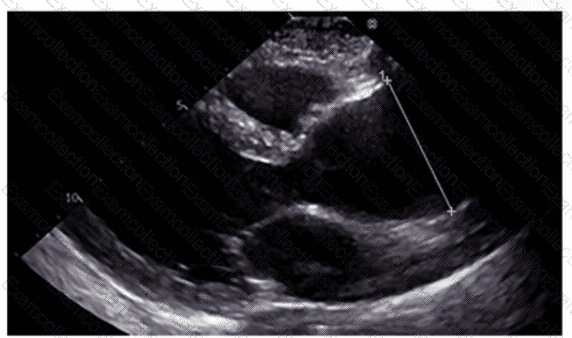

Which region of the aorta is being measured to assess the critical finding in this image?